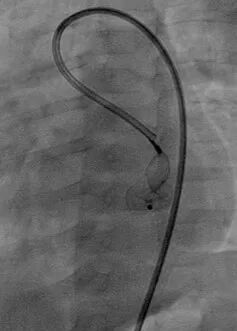

通过5F左冠造影管将0.032 in超滑导丝260 cm通过瘘口,进入下腔静脉后,使用网篮抓捕导丝建立轨道。